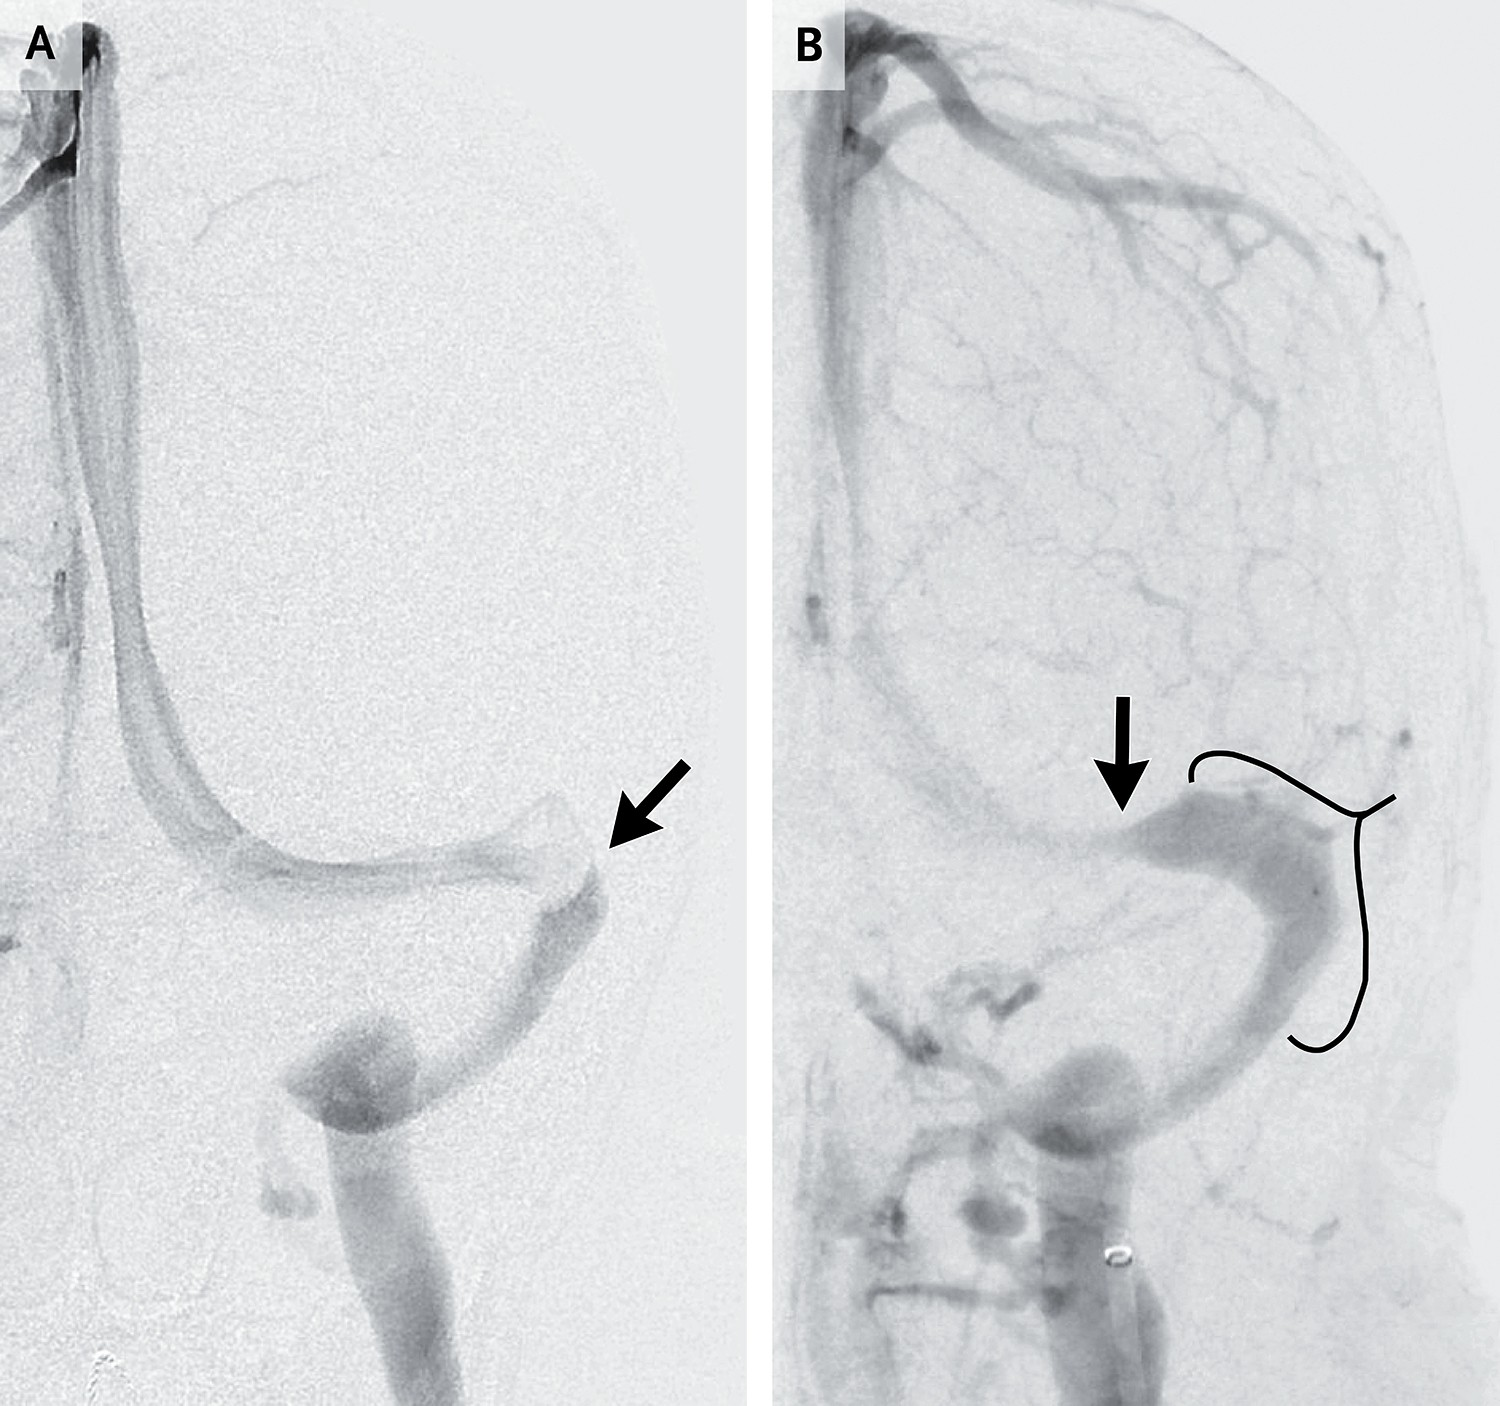

硬脑膜静脉窦支架置入术

实施硬脑膜静脉窦支架置入术时,患者需接受全身麻醉,介入放射科医师首先确认该区域存在明显静脉压梯度,随后将支架穿过影响优势横窦的狭窄部位28,69。该手术的优势在于可纠正解剖学阻塞,而这种阻塞被认为是导致ICP自我强化性升高的核心因素(图4)。在对19个已报道病例系列的汇总分析中,硬膜下血肿或脑内血肿风险较低(0.49%),但有两例死亡报告。该综述同时指出,CSF压力平均下降13.3厘米水柱70。患者术后需服用阿司匹林和氯吡格雷长达6个月,以预防支架内血栓形成。

静脉窦支架置入术最严重的局限性是部分患者虽然ICP降低,但未能恢复至正常范围。如果ICP仍然偏高,视觉功能可能继续恶化。由于接受双联抗血小板治疗的患者禁忌腰椎穿刺,因此支架置入术后无法立即检测初压。由于担忧支架疗效不完全,因此许多患者仍需持续服用乙酰唑胺。多项病例系列研究显示,15%的患者出现支架邻近区域新发狭窄(图5)。复发性狭窄表明ICP仍偏高,恰在需要缓解视盘水肿的时刻持续损害视盘。通常可通过二次支架置入术进一步降低ICP,但有时需行CSF分流术才能阻止视力减退。